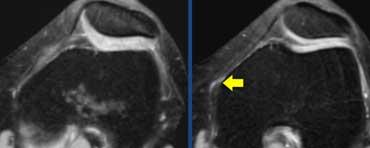

Hội chứng ma sát dải chậu chày: Dịch trong túi hoạt dịch thấy được giữa dải chậu chày và xương đùi (mũi tên vàng). Dịch khớp dừng lại tại các mũi tên đỏ.

Cùng bệnh nhân trên. Trên các lát cắt axial, có thể thấy dịch trong túi hoạt dịch nằm giữa dải chậu chày và xương đùi bên dưới.

Đôi khi cần phân biệt dịch tại vị trí này với dịch khớp.

Cần xem xét toàn bộ các lát cắt hình ảnh.

Trong trường hợp này, dịch khớp dừng lại tại các mũi tên đỏ.